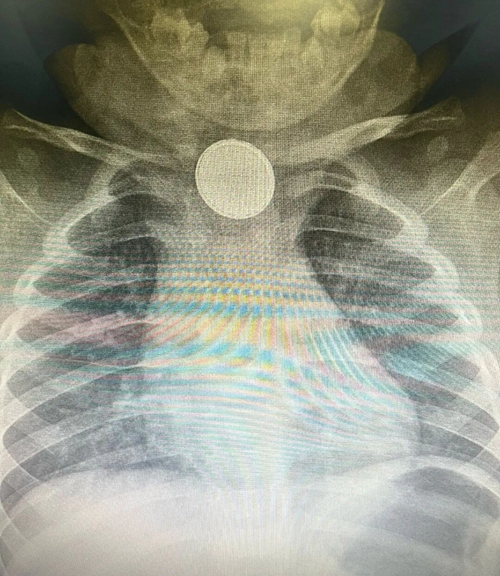

急诊医师凭借丰富经验,初步判断是消化道异物,当即安排检查。X 线片很快给出答案 —— 食管处可见出现一个类圆形高密度影。

类圆形高密度影